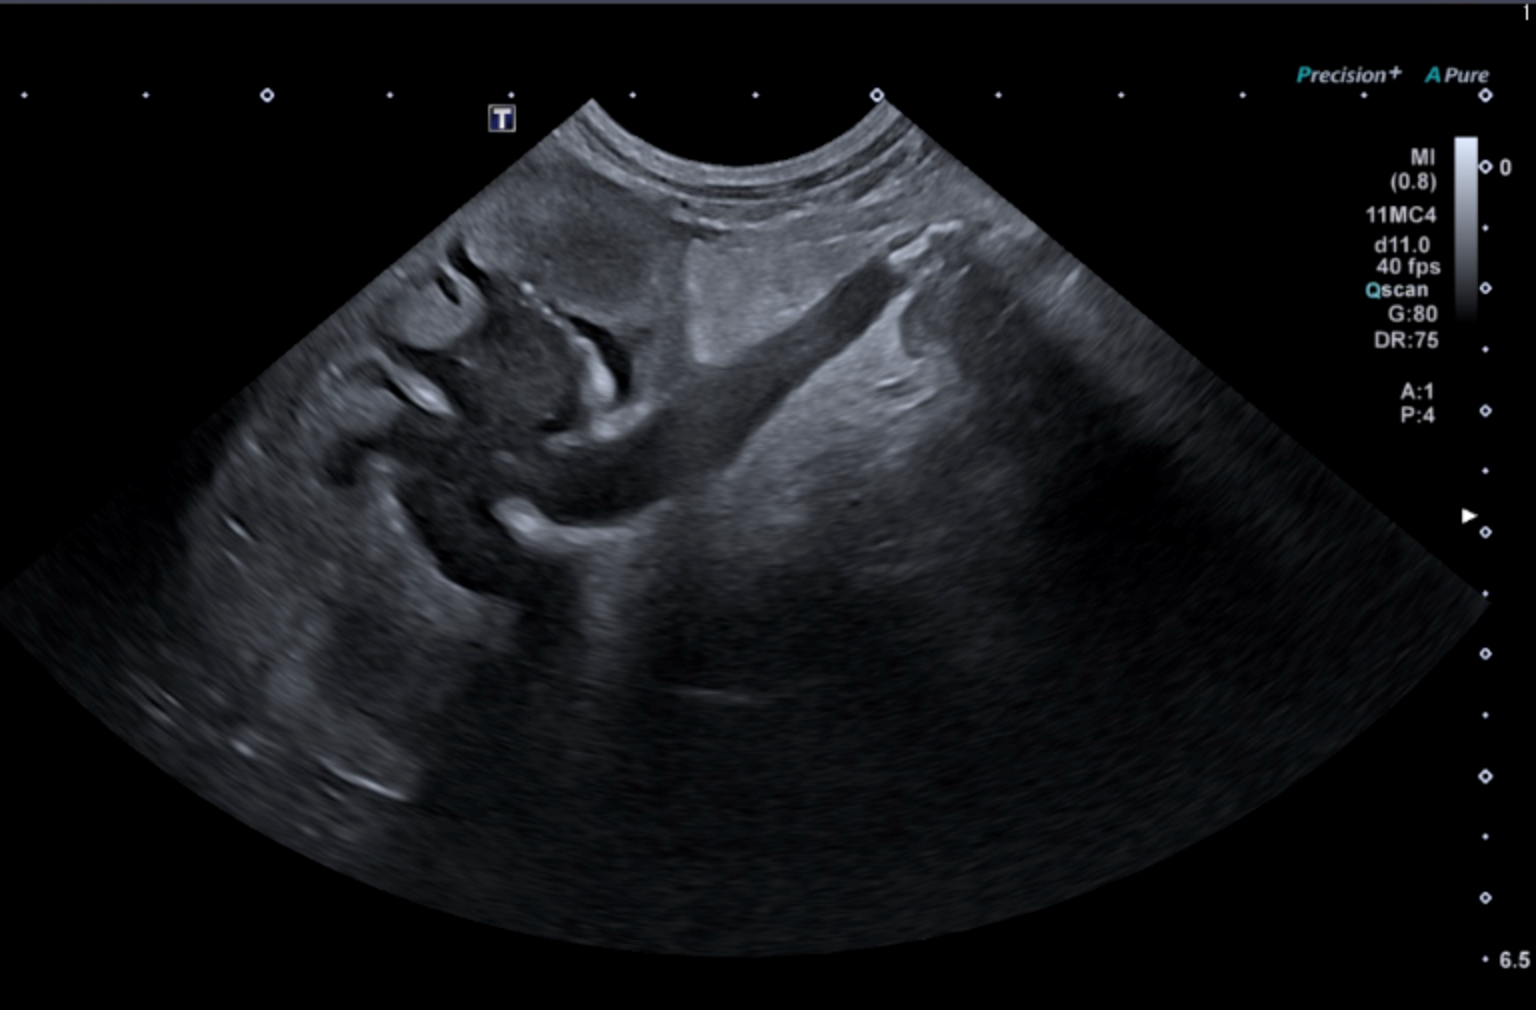

• Sémiologie échographique du tube digestif : signes clés et interprétation.

• Études de cas cliniques vidéo : identification, description, synthèse des anomalies digestives et diagnostic différentiel.

• Études de cas cliniques vidéo : analyse, description, interprétation des lésions et élaboration d’un diagnostic différentiel.